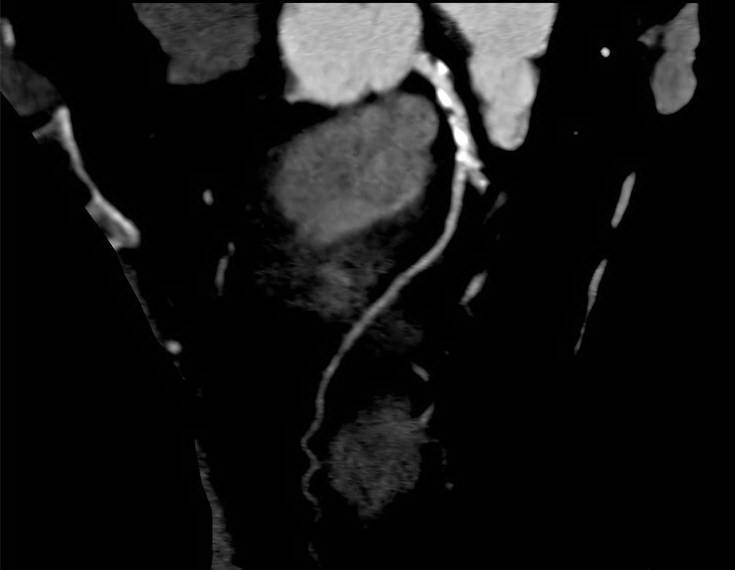

Case Study (70% LAD Block)

Case Study (70% LCX Block)

Case Study (Stent - LAD & LCX)

Case Study (Triple Vessel Block)

Cardiac CT

CARDIAC CT. Explained.